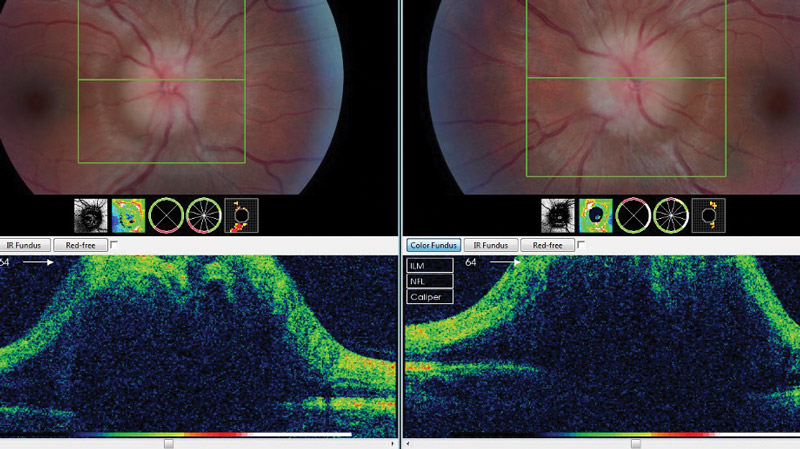

Figure 1: OCT scan of papilloedema patient with bilateral optic nerve swelling grade 3.

A 22-year-old female saw her local optician complaining of mild blurring of vision and generalised headaches. On assessment her visual acuity was slightly reduced at 6/7.5 in both eyes (0.1 on logMAR). Colour vision was full and visual fields testing showed enlarged blind spots. An OCT scan of her optic nerve showed bilateral optic nerve swelling (Figure 1). She was referred to the eye emergency clinic where her optic nerve swelling was confirmed. She was referred to the medical team where she had CT/CTv followed by an LP which showed raised opening pressure of 35cm of water (raised intracranial pressure). As there were no other causes, she was diagnosed with IIH. She was put on acetazolamide (250mg QDS) and followed up in the neuro-ophthalmology clinic until her papilloedema resolved. Weight loss advice was given and side- effects of treatment were explained and her acetazolamide was reduced gradually and she continues to be on regular follow-up until full remission.